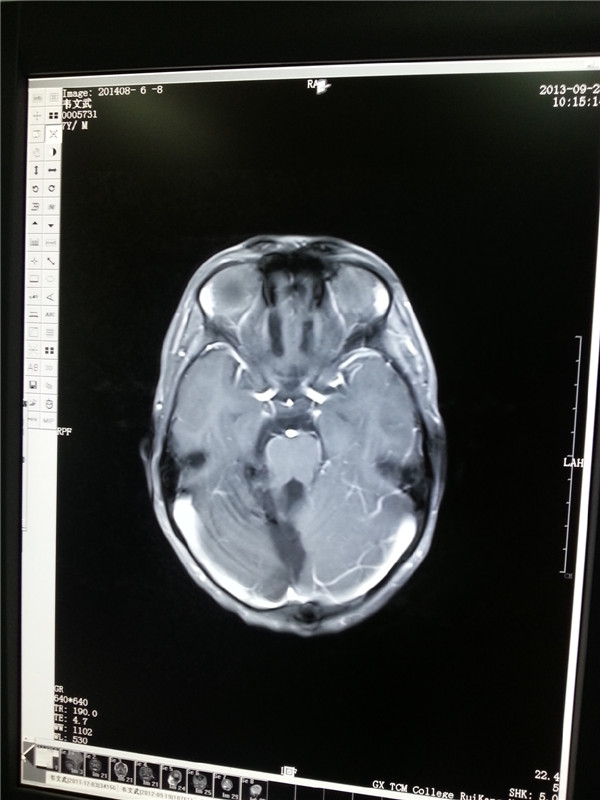

2013.9肿瘤消失(左图);2014.5复查肿瘤无复发(右图)